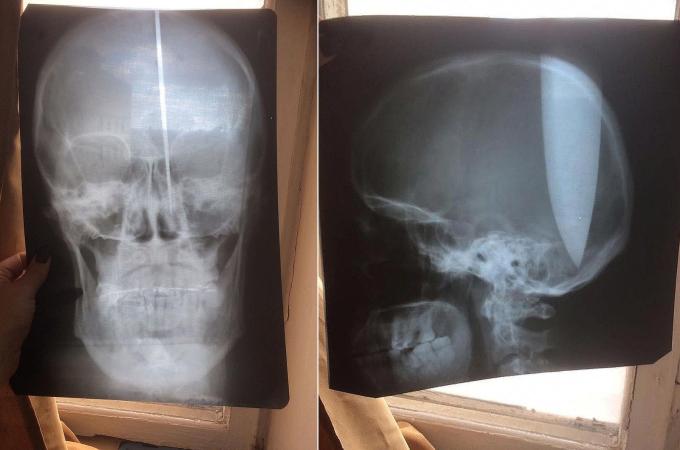

Psychicky narušený muž si do lebky zabodl dlouhý nůž: Nemohl prý dýchat

16.10.2018